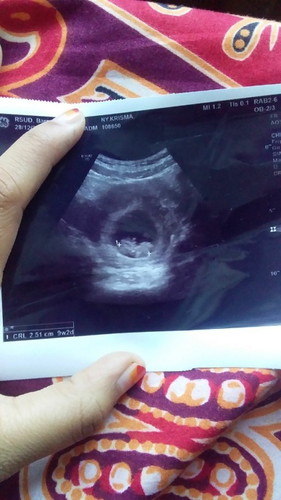

Assalamualaikum bun,mau berbagi cerita sedikit Jadi minggu kemarin saya dari USG karena waktu pipis,pipisnya warna merah dan keluarnya sedikit tapi sakit itu terjadi berulang kali cuman kalau air pipisnya udh berwarna merah terus pipis lagi selanjutnya udah ngk merah tapi masih sakit dan keluarnya sedikit sampai risih harus kluar masuk toilet tapi kata dokter bayi nya baik"saja dan sehat detak jntung nya juga.kalau bgitu kenapa yah bund?apa ada yang pernah rasakan jg?terus kata dokter udh 9w tapi perhitungan di aplikasi ini udah 11w,jadi bingung.

klo di aplikasi TAP kan bunda masukin nya dari HPHT bun... emg klo usg bgtuh bun krna berdasarkan berat janin yg di ukur.. sya aja waktu usg pas di 9 week tpi hasil usg 9w3 day.. hitungan HpHT udh 11w4d. tpi hitungan usg udh 12 week pas hari ini

diaplikasi lebih baik diganti HPL nya sesuai USG,bs kita atur kok, tp HPL dibawah 4-5 month msh berubah ubah sih, tp tiap abis USG ganti aja HPL nya